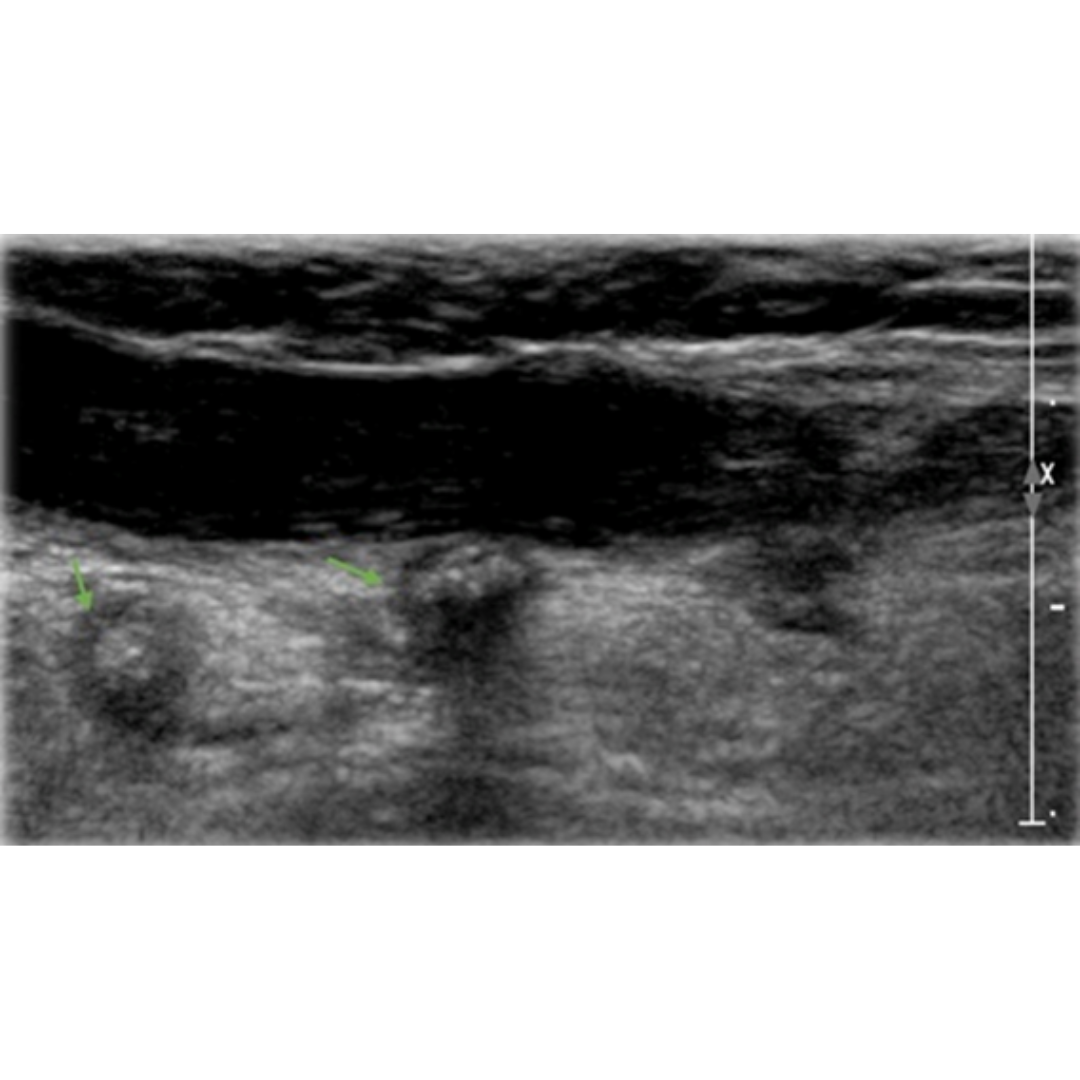

Figura 7. Flechas verdes indican granulomas, que se observan como imágenes hiperecogénicas con sombra acústica posterior y un tenue halo hipoecogénico.